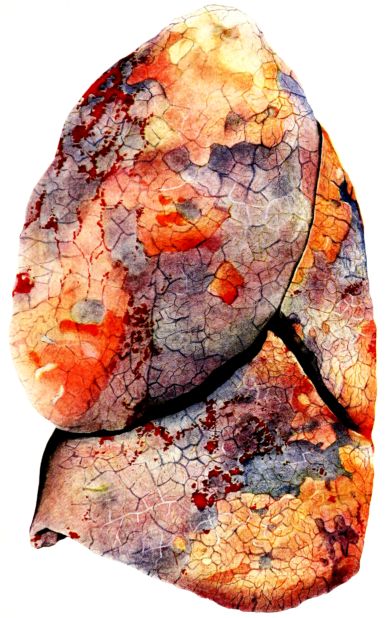

FIG. XIII. AUTOPSY NO. 96. RIGHT LUNG. A WATER COLOR DRAWING OF A GROSS LUNG IN THE ACUTE STAGE. NOTE THE SIZE OF THE LUNG, THE HEMORRHAGES ON THE PLEURAL SURFACE, AND THE BLUE AREAS OF CONSOLIDATION.

FIG. XIV. AUTOPSY NO. 96. LEFT LUNG. NOTE ITS SIZE AND THE PATCHY CONSOLIDATION.

19The lungs are extremely voluminous (12, 17) due in part to an accumulation of liquid within them. This finds its way into the trachea and completely fills the latter structure with blood-stained, syrupy fluid, with purulent material, or with a mixture of these (2, 90, 107, 157, 162). At first the pleural surface is smooth and often quite even, but on closer inspection, a minute granulation is suggested. In many cases even close examination does not allow the conclusion that an exudation of anything but serum has occurred through this membrane, except in localized foci. These foci more frequently involve the interlobar pleura and that of the lower lobes (112, 143). The volume of the lungs, often great enough to obliterate the pericardial area, is one of the two most characteristic features of the external examination. The other feature is their color. Small, bright red hemorrhages may occur anywhere. The larger patches are the most striking. Violet, purple, or dark brown areas, irregular in shape and distribution, are more frequently found on that portion of the pleura over the lower two-thirds of the lung. Between the deeply colored zones, there are pale pink areas which involve the lowermost edge to the least degree, the anterior margin somewhat more, and the apex of the lung most of all. The darker portions just referred to may project above the surface and may be circumscribed, resembling huge, fresh hemorrhagic infarcts (41, 108). The alveolar walls are not seen through the pleural surfaces in these darker zones. The pale pink areas, usually at the level of the more intensely colored zones, may be elevated and the dilated air sacs are distinctly made out through the pleura (Fig. XIII). At the hilum, the lymph glands are large and soft. When cut, fluid escapes and is often blood-stained. The cross section may present a distinct, diffuse, hemorrhagic appearance (162). At the hilus, too, the lymphatics, distended here and there over the surface of the pleura, are most affected. The congested bronchial mucous membrane and the exudate in these structures has been described.

After removal, the lung retains its shape, but is more flaccid than the consolidated lung of lobar pneumonia. It cuts with very little resistance and immediately a large amount of a syrupy, pink fluid escapes and obscures the entire area. With the fluid scraped away, the variations in the consistency of the lung become visible. The pale areas around the borders and chiefly at the apex in which the air sacs are discernible with the naked eye, sink slightly below the remainder of the surface, and the pleural edge inverts. The individual lobules of the lung in these areas are more conspicuous than normal, because the interstitial tissue bearing the lymphatics and vessels, as well as that around the bronchi and larger blood vessels, does not lose its edematous appearance as quickly as the alveoli (40, 92, 110, 164), and, consequently, these grey lines and points stand up somewhat more prominently.[6] In contrast with the paler areas which are prone to slight collapse, the remainder of the cross section retains its more smooth and even surface. The alveolar walls are not distinctly made out, but the terminal bronchioles often make themselves evident by the nature of the material which is within and by their distinct dilatation (1, 67, 110, 149, 162). The more firm areas stand out, too, on account of their difference in color. The scheme is not unlike that seen on the pleural surface, and while dark, almost black, infarct-like areas occur on the cut surface, the solid areas are more likely to be translucent, dull, light red, brown or even grey. They have a surface similar to a very fresh, tuberculous, gelatinous pneumonia, but the color differs from the cloudy grey of the latter on account of the admixture of blood in the exudate and the great congestion of the vessels (Fig. XIV).

The well developed post-mortem muscular rigidity, the lividity of the dependent parts, of the face with its mucous membranes, and often of the trunk, the jaundice variable in extent, the crusts of blood on the nares and mouth, and the splanchnic dilatation are features which prepare for the gross picture presented by the thoracic organs. The increased moisture within the pleural cavities associated with the even, translucent pleural surface, whose dilated lymphatics become more and more prominent towards the hilum, the large succulent lymph glands, and the exudate in the bronchial tree, are all striking, but more characteristic of the gross picture, is the great increase in volume of the lung itself, mottled 20with brilliant colors. The lung, too, is very wet and on section, after the syrupy, blood-stained fluid escapes from the less definitely consolidated zones, the latter appear, not as the usual granular, firm areas of hepatization, but have more the consistency of a gel, and also its translucence. Characteristic of this disease as these changes may be, the specificity of the fundamental lesion in the respiratory tract, becomes more emphatic after study of its histology (92, 162).